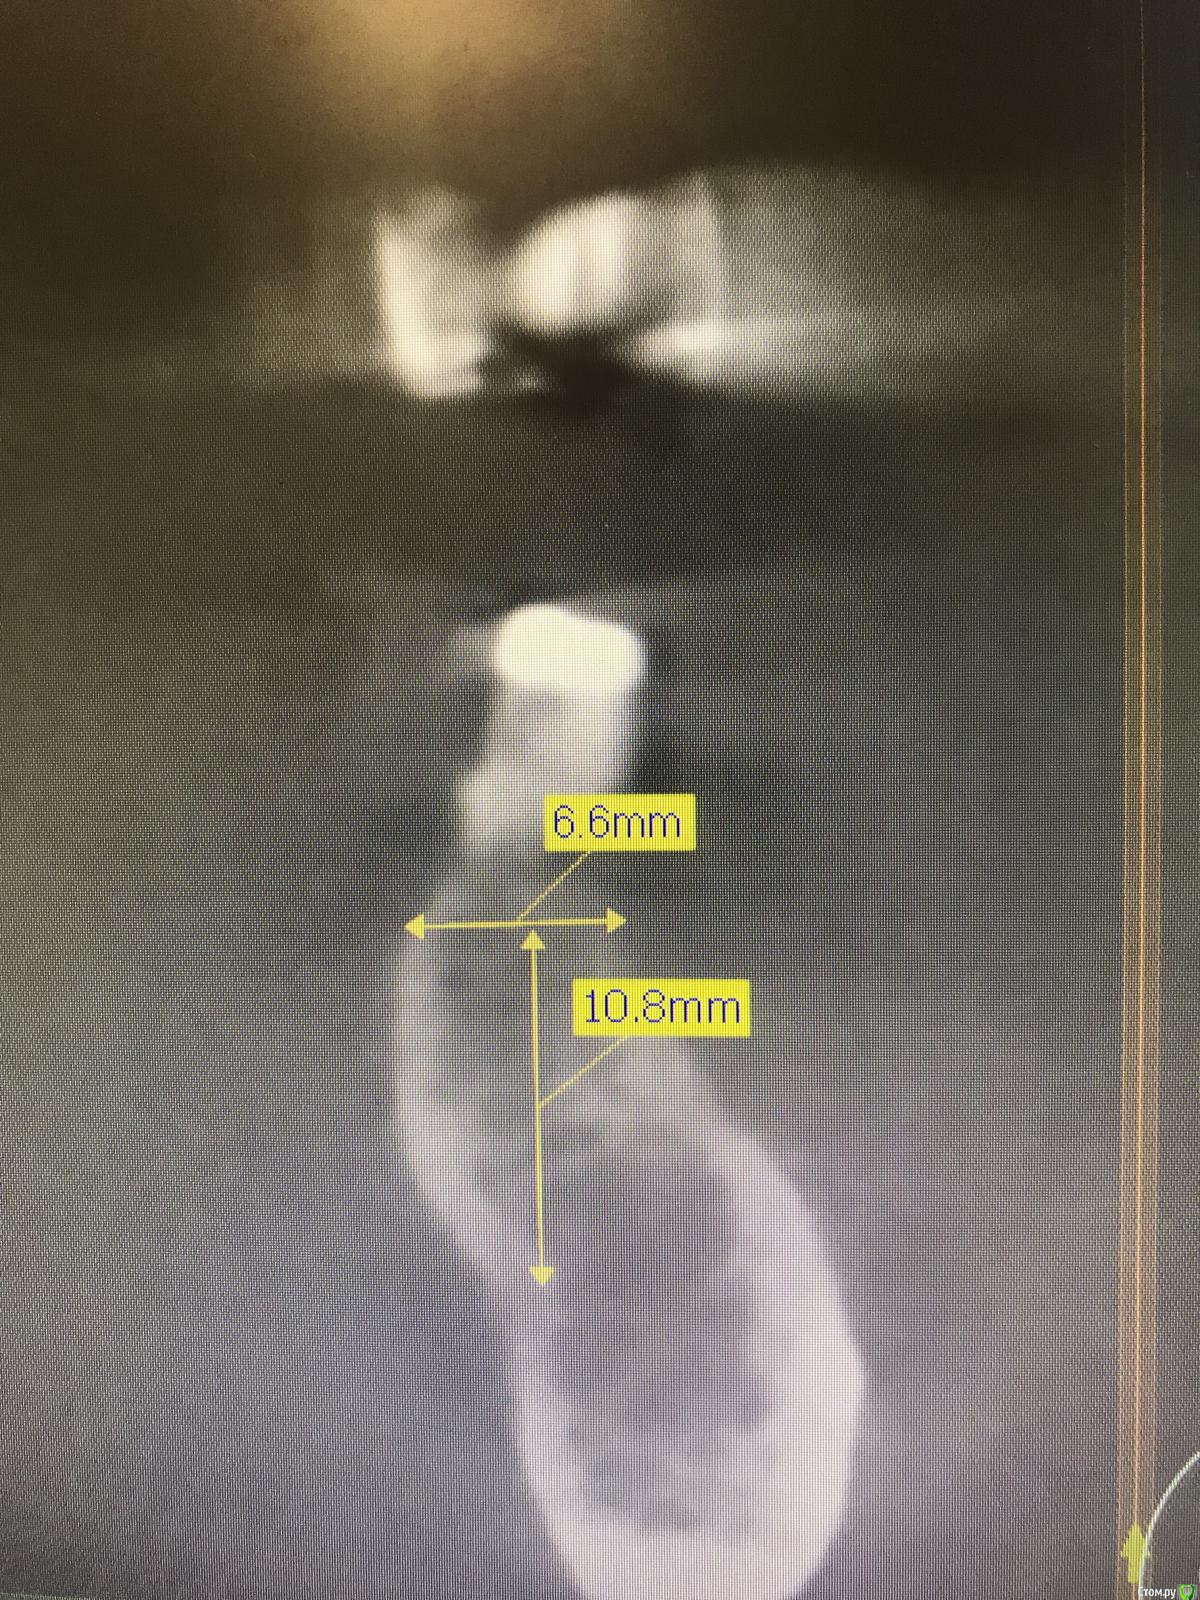

Santi Опубликовано 19 сентября, 2018 Автор Поделиться Опубликовано 19 сентября, 2018 Кт до 34, 3644,46 Ссылка на комментарий